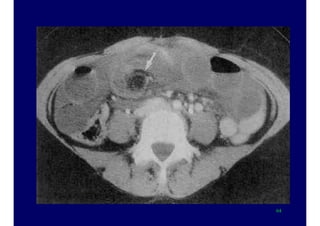

Colonic perforation

50